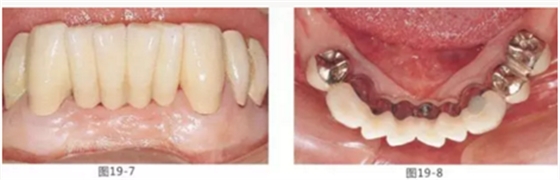

圖19-7 佩戴最終修復(fù)5年后的唇頰側(cè)面照。

圖19-8 同時期下側(cè)咬合面照。